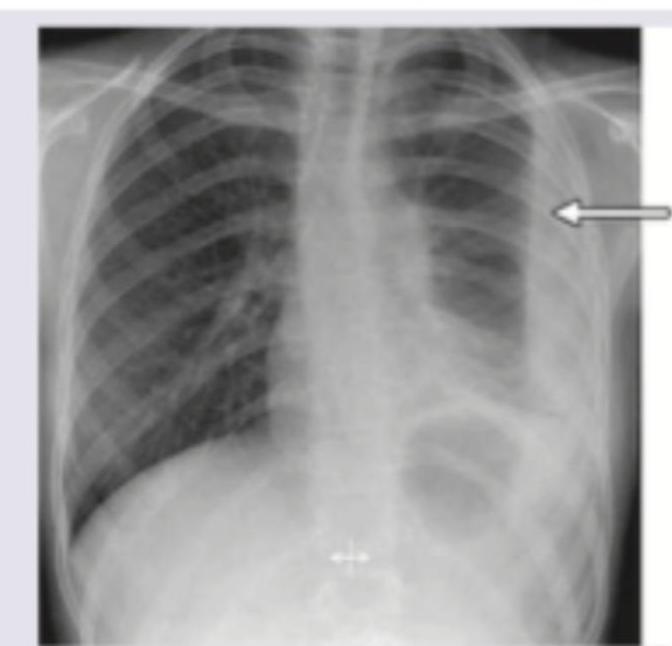

A 10-year-old child presents with fever, chills, rigors and fast, difficult breathing. The image shows:

Explanation: ***Bacterial pneumonia with rupture of pneumatocele*** - The image shows a **large air-filled cystic lesion** (pneumatocele) in the left lung with evidence of surrounding **consolidation**, consistent with bacterial pneumonia. The arrow points to an area that suggests communication with the pleural space, indicative of rupture. - The clinical presentation of **fever, chills, rigors, and difficult breathing** in a child is highly suggestive of a severe bacterial lung infection, which can lead to complications such as pneumatoceles and their rupture. *Pleural effusion with collapse of lower lobe* - While there is some opacity on the left, the predominant feature is a **large air-filled cyst** rather than diffuse fluid collection. - A simple pleural effusion would typically show a **meniscus sign** and does not explain the large lucent area, which is characteristic of a pneumatocele or bulla. *Pneumonia with collapse* - Though there is evidence of pneumonia with consolidation, the key distinguishing feature here is the **large cystic structure (pneumatocele)**. - Lung collapse would present as significant **volume loss** and shifting of mediastinal structures, which is not the primary radiographic finding in this image. *Asthma* - Asthma is a **bronchospastic condition** and typically presents with hyperinflation on chest X-ray during an exacerbation, without discrete pulmonary lesions like pneumatoceles or consolidation. - The clinical symptoms of **fever, chills, and rigors** are not typical for uncomplicated asthma, but rather point towards an infectious etiology.